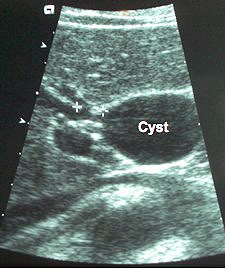

Ultrasound picture of a choledochal cyst (i.e. a balloon-like swelling of the bile duct) in a 35-years old woman. Over her lifetime, she would have a higher-than-average risk of developing a bile duct cancerRisk of bile duct cancer is increased by fibrocystic disease of the liver (called Caroli’s disease), choledochal cysts (i.e. bile duct cysts) and abnormalities of the junction of the pancreatic and bile ducts. Environmental factors like exposure to toxins such as Thorotrast (a radiologic material used in the 1950s), and industrial toxins such as dioxins and polyvinyl chloride also increase the risk. Liver fluke infestations in the Far East are associated with the high incidence of intrahepatic cholangiocarcinomas in those areas. Smoking and alcohol consumption further increases this risk in these ethnic groups. Hepatitis C seems to have a link. Underlying cirrhosis increases the risk of intra-hepatic cholangiocarcinomas. In the West, the best known predisposing factor is primary sclerosing cholangitis (PSC), a chronic inflammatory disease of the bile ducts, which carries a life-time cancer risk of 9-23%.